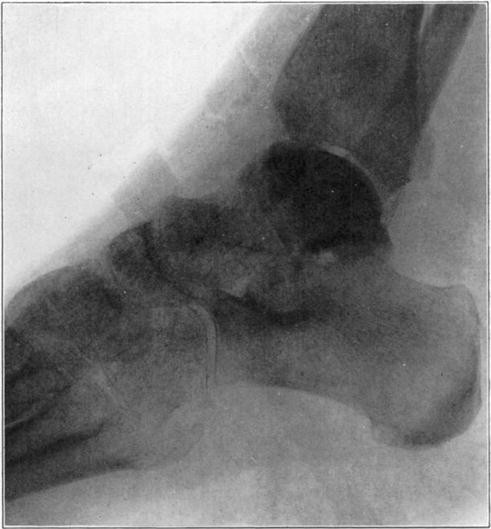

Necrosis of Os Calcis

In fracture of the neck of the os calcis the body may rarely have so much of its blood supply cut off that it undergoes extensive necrosis. Its subsequent history is analagous to that of a necrotic proximal fragment in intracapsular fracture of the neck of the femur. If bony union between the fragments follows, the necrotic body will be invaded gradually by blood vessels, fibrous, osteogenic, and myelogenous tissue, and a gradual replacement of the necrotic by living elements will be brought about. The replacement may be incomplete and the necrotic portion located farthest from the fracture may be broken down by weight-bearing before the ingrowing tissue reaches it, thereby leading to deformity and permanent derangement of the bone.

The following cases are illustrative of this condition.

Case 2. Seventy-four days after fracture of neck of astragalus, posterior dislocation of body, and reduction by operation. Body necrotic and retained normal density. Atrophy of disuse of other bones. Bony union of fracture.

Case 2. One hundred and sixty days after fracture. Body slightly reduced in density near fracture due to invasion from neck.

Case 3. Fresh fracture of neck of astragalus and chip off superior and posterior portion of os calcis.

Case 3. Two hundred and seventy-four days after injury. Fracture of astragalus united. Superior and posterior part of body broken down and irregular while remaining portion dense and transformed. Indicative of necrosis of body with secondary changes.

Case 3. Eighteen months after injury, showing a defective but gradually reforming articular portion of the body of the astragalus.

The blood supply of the astragalus is derived mainly from a branch of the arteria dorsalis pedis which traverses the sinus tarsi lateral to the neck and breaks up to enter the bone near the junction of the neck and body along the lateral and inferior surfaces. There are very small branches entering the bone mesially and posteriorly at points of ligamentous and capsular attachments. Apparently when there is a fracture along the junction of body and neck the important vessels to the body are interrupted and there may be insufficient circulation through the remaining vessels, so that aseptic necrosis of a large part or all of the fragment follows. It is evident from the partial collapse which occurred in Case 3 that when necrosis of the body is diagnosed, the limb should be protected from weight-bearing for at least several months,—until union, revascularization, and transformation of necrotic area has been largely brought about. It seems probable that some of the bad results that have been reported in fracture of the neck of the astragalus, either united or ununited, have been due to overlooked aseptic necrosis of the body.